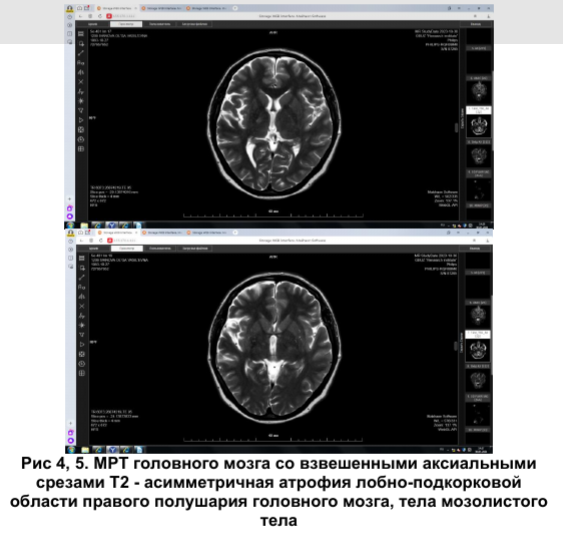

По данным проведения МРТ (рис.4,5) головного мозга в правой лобно-подкорковой области, теле мозолистого тела определяется зона умеренно повышенного сигнала на FLAIR, изо-, гипоинтенсивного сигнала на Т1-ВИ, к которой слегка подтянут правый боковой желудочек (кистозно-глиозные изменения). Очагов патологического контрастирования не выявлено. МР-картина изменений головного мозга соответствует нейродегенеративному процессу.

По данным МРТ головного мозга, выявленный асимметричный патологический процесс, локализованный преимущественно в правой лобно-подкорковой области и теле мозолистого тела, расценен как нейродегенеративный. Интересно, что при описании изменений в мозолистом теле, характерных клинических симптомов выявлено не было.